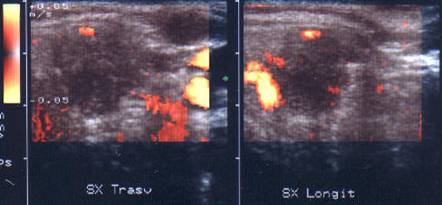

Aceeasi pacienta ls doppler color - vascularizatie intensa

a lobului stang.

Femeie de 76 ani. Tiroida de dimensiuni crescute,

suprafata neregulata, cu consistenta dura.

Hipotiroidism primari (TSH=76 mcUI).

Glanda marcat hipoecogena, cu trabecule hiperecogene de fibroza.

Aceeasi pacienta. Hipervascularizzatie difuza (tip IV)

Aceeasi pacienta. Piesa operatorie. Examen citologic prin citoaspiratie: Marcat infiltrat flogistico linfoid; componente epiteliale cu aspect oncocitar fara atipii; Examen histologic postoperator: Tiroidite Hashimoto.